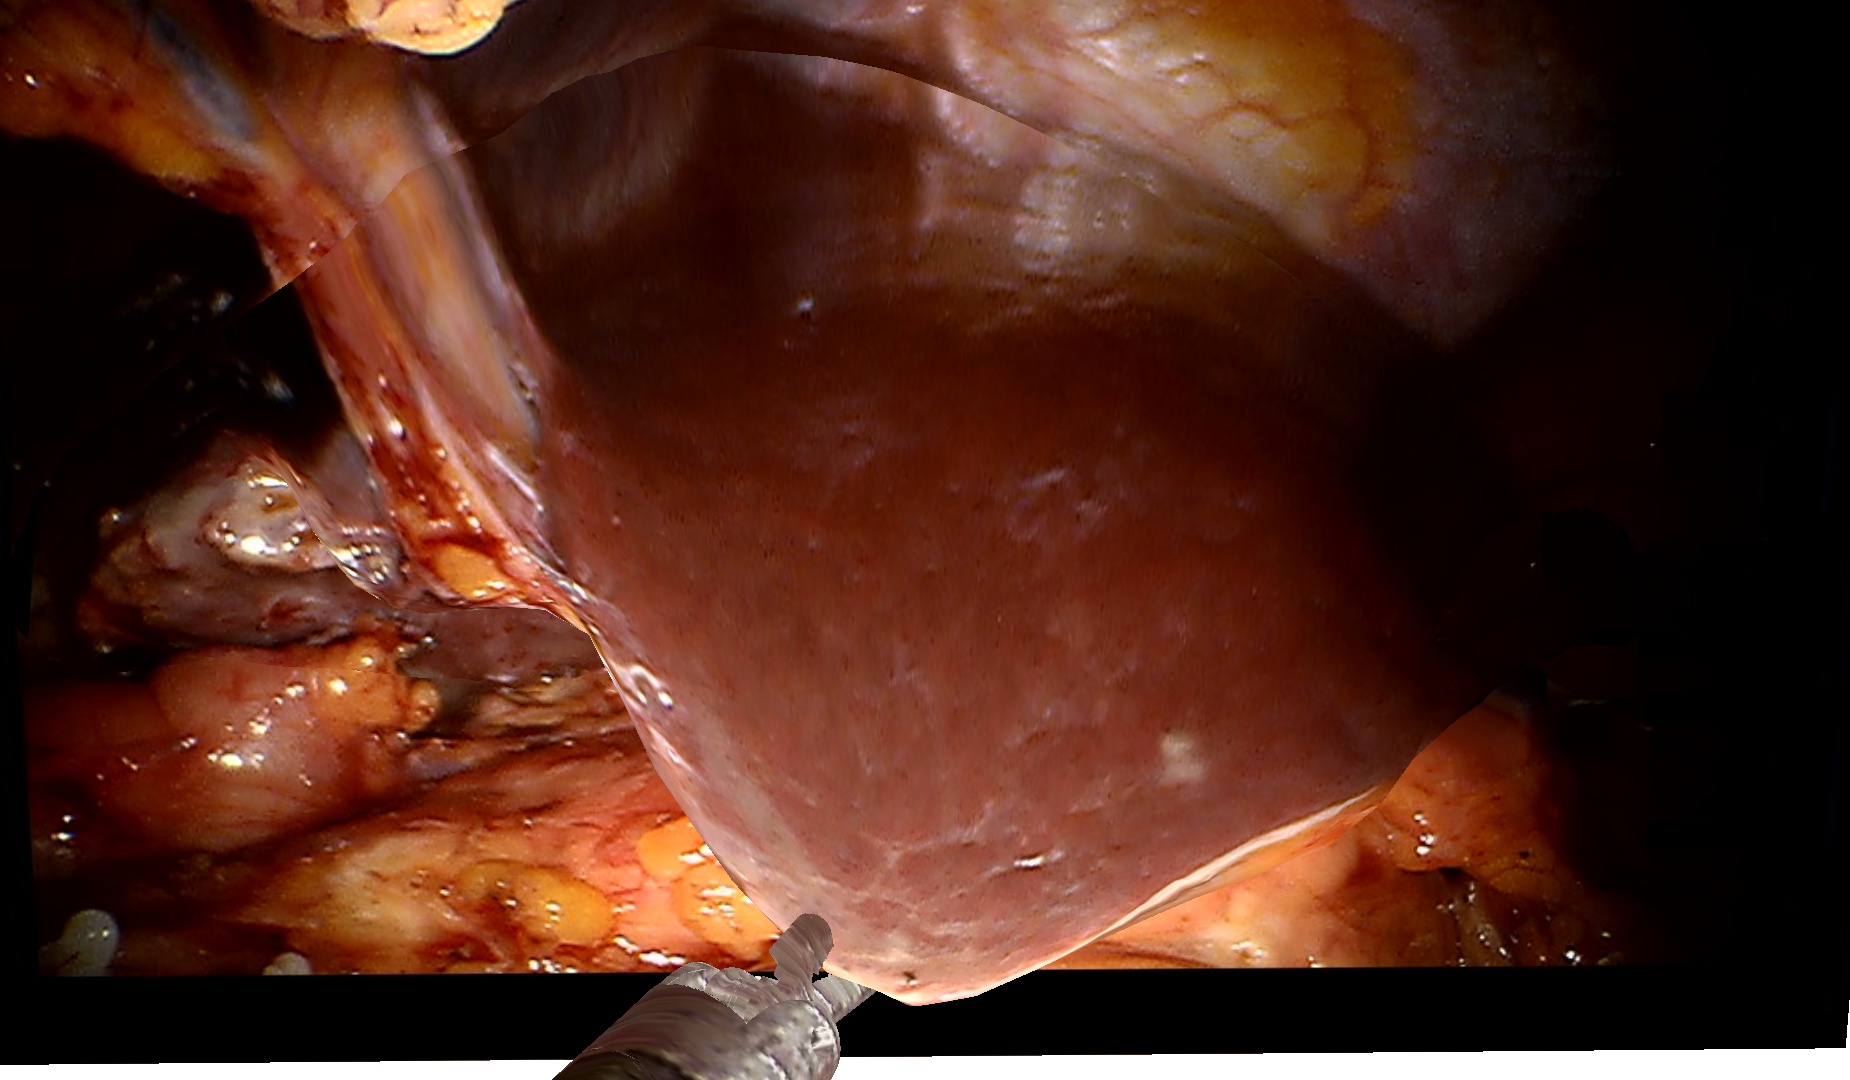

3.0.2 Qualitative Evaluation on Clinical Data

To demonstrate the effectiveness of our method on clinical data, we use a dataset of two visceral pig surgeries with a preoperative post-insufflation CT, initial rigid registration, a tracked laparoscope, and corresponding 2D monocular RGB videos. Surgical tools were masked out using SurgicalSAM [23]. The first sequence from the first surgery shows a tool-tissue interaction, whereas the second one shows a breathing motion without external manipulation. Because there is no deformed ground truth, as measuring intraoperative deformation would require intraoperative scanning, we demonstrate qualitative results.

Figure˜4 shows results on the tool-tissue interaction. The surgical tool presses down on the stomach, leading to the deformations tracked in the deformed mesh and CT (bottom rows). Although the difference in pressure applied between B and C appears marginal, we successfully track the increasing deformation, the difference being visible in both mesh and CT. For D and E, the tool is repositioned, now pulling the stomach back. Note how this backward pull is visible in the respective deformed CTs by a deformation to the right, since the laparoscope captures the scene roughly in the coronal plane, whereas the CT slice is shown in the sagittal plane.

Figure 4: Examples from a tool-tissue interaction sequence. Rows from top to bottom: input images acquired by the laparoscope, images rendered with our method, deforming mesh, and deforming CT. Arrows in A point to the deforming anatomical structure, circles in B highlight the area of deformation, and arrows in E visualize the pull direction. See video in the supplementary material.

Since we rely on an initial registration, we are also subject to registration errors. There is a slight misalignment between the structure being manipulated in the input images (stomach) and the deforming mesh. Also note that we initialize our mesh from a post-insufflation CT, ensuring that the initial mesh and the intraoperative state early in surgery are still very similar. Regarding the deformation of the CT, we can only capture surface deformations by deforming our mesh. A more realistic deformation of deeper layers would require biomechanical modeling. Apart from those caveats, the method does not work in real time yet. Given the strides being made in the 3D computer vision community around 4DGS, we are confident that this problem will be solved soon. Despite those limitations, the deformations of the stomach in the CT are sensible and correspond to the tool-tissue interaction as confirmed by a board-certified surgeon.